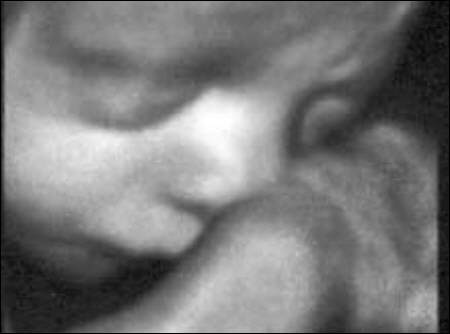

Aufgrund einer hohen technischen Ausstattung in meiner Ordination ist es mir möglich ein dreidimensionales Bild von Ihrem Kind anzufertigen. Die Kindsbewegungen können „live“ am Bildschirm mitverfolgt werden (4D).

Dieses ermöglicht einerseits die bessere Diagnostik einiger Fehlbildungen wie etwa der Lippen-Kiefer-Gaumenspalte, andererseits kann so das erste "Foto" von Ihrem noch ungeborenen Kind gemacht werden, was die Mutter-Kind-Beziehung zusätzlich fördert und sicherlich eine nette Erinnerung an diese außergewöhnliche Zeit ist.

Ein 4-D-Bild |